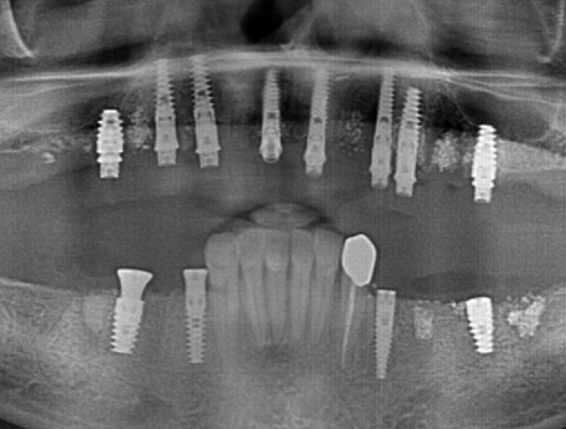

The implants were placed immediately following tooth extraction. They were positioned subcrestally — 2–3 mm below the bone crest — to allow for anticipated bone remodeling. A total of eight implants were placed in the maxilla and four in the mandible.

| Tooth Position (FDI) | Implant System | Size (Ø x L) and Purpose |

|---|---|---|

| #11, #12 | XGATE Dental | 3.75 x 15.2 mm (Anterior Maxilla) |

| #34 | XGATE Dental | 4.2 x 10 mm (Mandibular Premolar) |

| #16, #26 | DSI Implants | 5.0 x 10 mm (Molar Region) |

| #13, #14, #23 | DSI Implants | 3.75 x 15.2 mm (Anterior/Premolar Region) |

| #36, #45, #47 | DSI Implants | 4.2 x 10 mm or 5.0 x 10 mm (Mandibular Region) |

| Total: 12 Implants | 3 XGATE, 9 DSI (Correction: 8 DSI) | Optimal Prosthetic Support |

Implant dimensions were selected based on the patient’s anatomy and the anticipated functional load in each area:

- Molar region: 5.0 x 10 mm

- Anterior region: 3.75 x 15.2 mm

- Mandibular premolar region: 4.2 x 10 mm